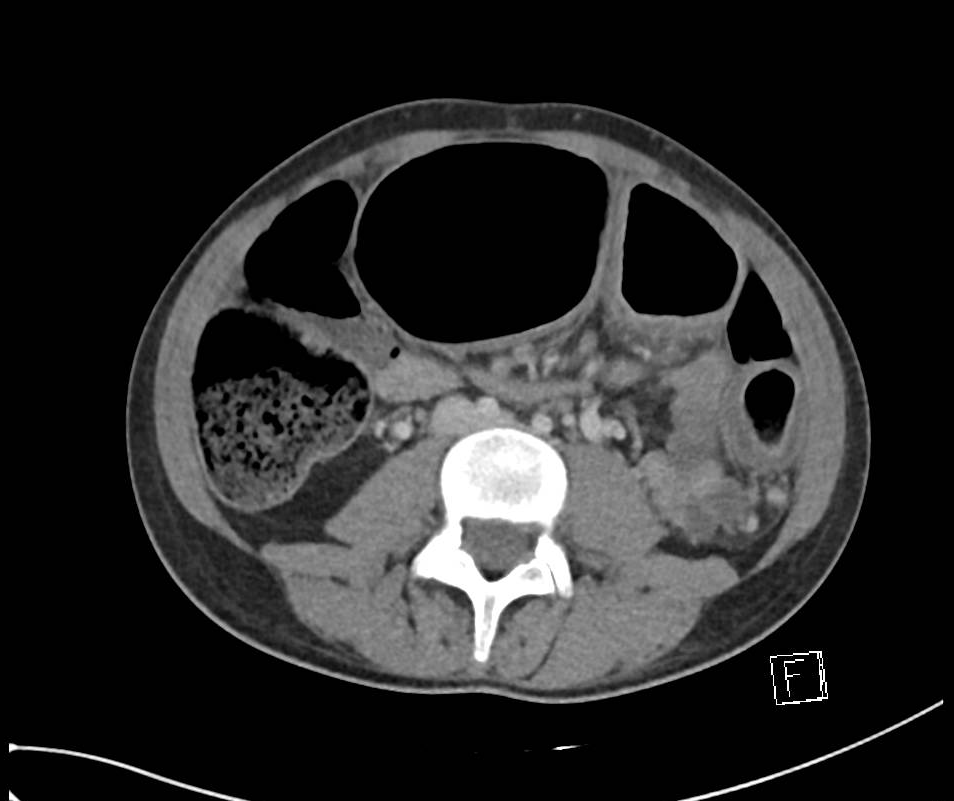

肠壁增厚的ct诊断

图片尺寸900x607